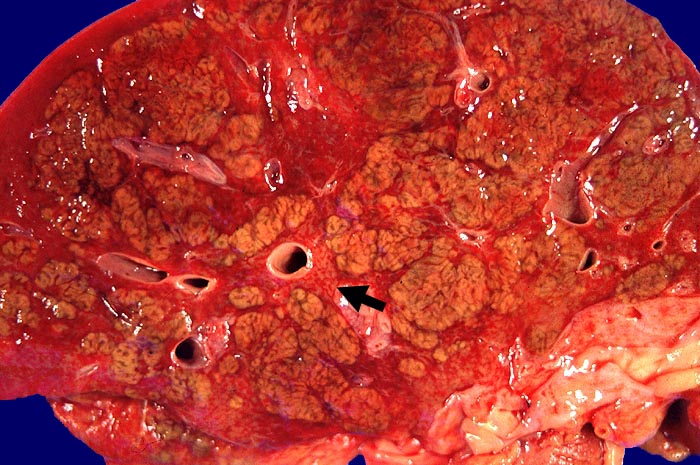

Morphologie:

• Regelrechte Läppchenarchitektur.

• Lobuläre gemischte Entzündung.

• Ansammlungen zeroidbeladener Makrophagen innerhalb von Parenchymnekrosen (abgebaute fleckförmige Nekrose).

• Apoptosen (hypereosinophile abgerundete Leberzellen).

• Portale gemischte Entzündung.

• Fehlende Fibrose.